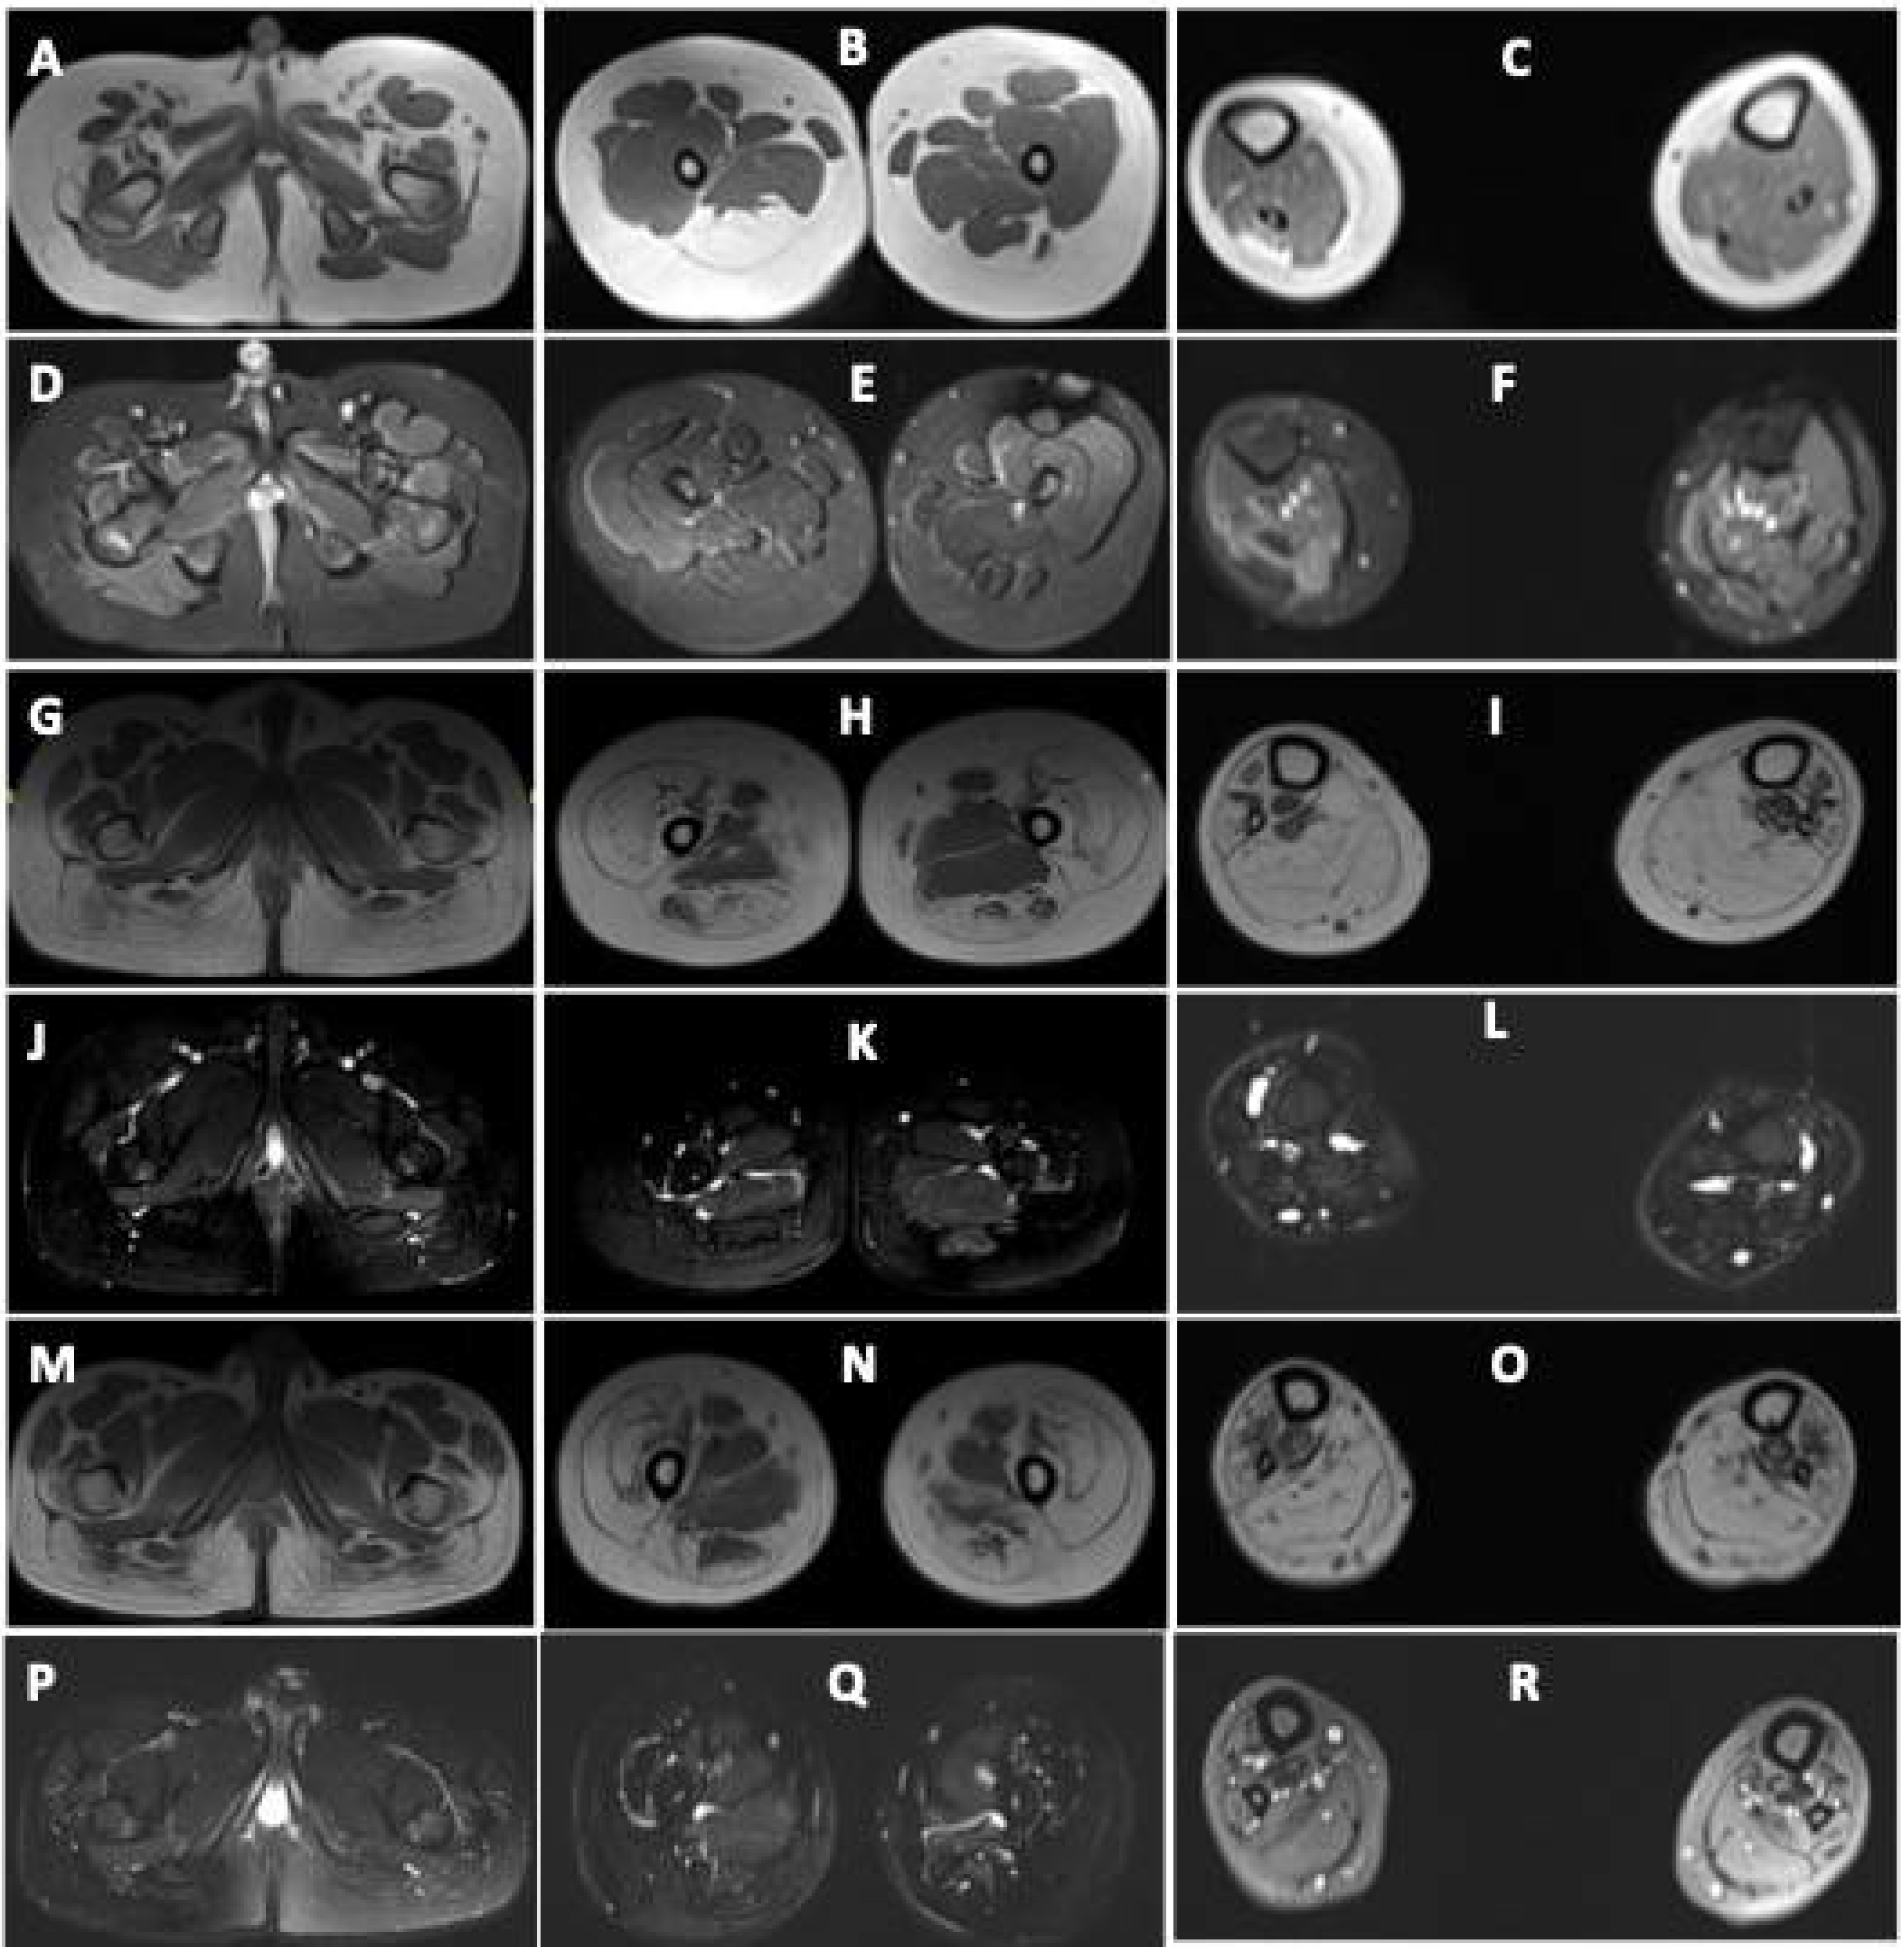

Figure 2.

Muscle MRI images of patients with DA5D: (A–F) muscle MRI images of patient 1: axial T1-weighted sections at the level of the (A) pelvis, (B) midthigh, and (C) midleg reveal volume loss with fatty replacement, most pronounced in bilateral tensor fascia lata (Mercuri Grade 3), right semimembranosus (Grade 3), semitendinosus (Grade 3), bilateral biceps femoris (Grade 2b). Grade 2a fatty replacement is seen in the lateral compartment of the right leg and gastrocnemius. Axial fat-saturated T2-weighted sections at the level of the (D) pelvis, (E) midthigh, and (F) midleg reveal no edema; (G–L) MRI images of patient 2 and (M–R) of patient 3: axial T1-weighted sections at the level of the (G,M) pelvis, (H,N) midthigh, and (I,O) midleg reveal volume loss with fatty replacement, most pronounced in bilateral gluteus maximus (Mercuri Grade 3), vasti (Grade3), rectus femoris (Grade 2a), semimembranosus (Grade 2b), semitendinosus (Grade 2b), biceps femoris (Grade 2b). Grade 2b fatty replacement is seen in the anterior, lateral, and deep posterior compartments of the legs. The superficial posterior compartment of both legs reveals Grade 4 atrophy with fatty replacement. Axial fat-saturated T2-weighted sections at the level of the (J,P) pelvis, (K,Q) midthigh, and (L,R) midleg reveal no fluid signal.

Muscle MRI in both revealed volume loss with fatty replacement, most pronounced in bilateral gluteus maximus, vasti, rectus femoris, hamstrings, and all muscles of the anterior, lateral, and posterior compartments of legs. Hip adductors and sartorius were spared (Figure 2).

There are only a few reports on muscle MRI in patients with DA5D [4,11]. Severe fatty infiltration of thighs affecting the biceps femoris, sartorius and vastus lateralis, extensor digitorum longus, and asymmetric involvement of distal leg muscles with sparing of rectus femoris and gracilis has been reported [4,11]. All three patients in the current study underwent muscle MRI. Diffuse fatty infiltration was observed involving hamstrings and gastrocnemius in all, and extensive fatty infiltration of gluteus maximus, quadriceps, anterior, lateral, and posterior compartments of legs was also observed in the two monozygotic twins. This further implies a wider spectrum of disease involvement. It is interesting to note that the severity of muscle weakness was different in patients 2 and 3, but the severity of MRI findings was almost identical.